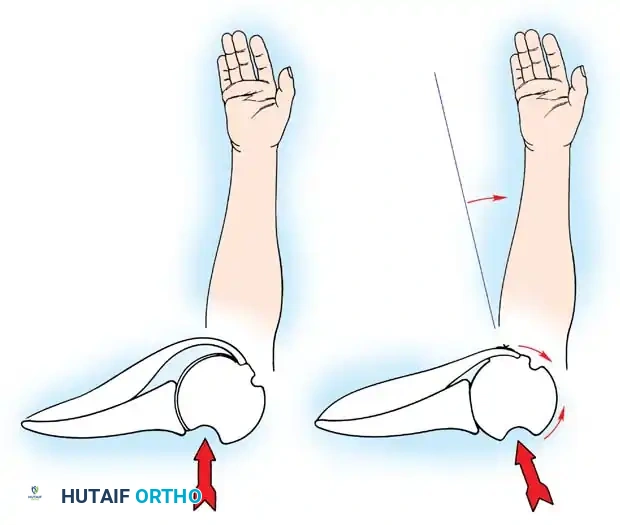

A Hill-Sachs lesion is an impaction fracture of the posterolateral humeral head, created when the head is driven against the hard anterior glenoid rim during dislocation. Burkhart and DeBeer introduced the concept of the "engaging" Hill-Sachs lesion, which levers the humeral head out of the joint when the arm is abducted and externally rotated.

Concurrently, anterior glenoid rim fractures or attritional bone loss can occur. Itoi demonstrated that a 20% loss of the anterior glenoid width critically compromises stability, rendering soft-tissue repairs (like an isolated Bankart repair) biomechanically insufficient. Advanced imaging (3D CT or MRI arthrography) is mandatory to quantify bone loss.

Hovelius further emphasized the frequency of recurrence in younger patients, particularly athletes, noting that the duration of post-injury immobilization did not significantly alter the natural history of instability. Instead, the degree and location of the initial trauma strongly correlated with recurrence. While Itoi et al. suggested that immobilization in external rotation may theoretically reduce recurrence rates by tensioning the subscapularis and reducing the Bankart lesion, the presence of structural damage often dictates the outcome. Burkhart and DeBeer, Sugaya et al., and Itoi et al. have definitively shown that glenoid bone loss exceeding 20% results in critical bony instability. This critical bone loss diminishes the "safe arc" of humeral rotation provided by the glenoid, leading to catastrophic instability when the deficient anterior edge is loaded at extremes of motion.

CLINICAL PEARL: The biomechanics of the IGHL complex are dynamic. With external rotation and abduction, the hammock shifts anteriorly and superiorly; the anterior band tightens to prevent anterior translation, while the posterior band fans out. Conversely, internal rotation tightens the posterior band. The anteroinferior band is the primary restraint to anterior translation at 90 degrees of abduction and external rotation (the classic apprehension position).

Turkel et al. demonstrated that true anterior dislocation cannot occur if the IGHL remains intact. Furthermore, Warren introduced the "circle concept," proving that for significant anterior translation to occur, there must be concomitant disruption or plastic deformation of the posterior capsular structures.